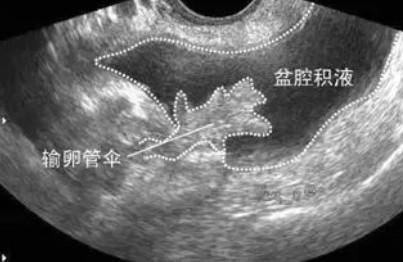

经常有女性朋友拿着她妇科彩超上“盆腔积液”的诊断结果来咨询:盆腔积液是什么病?需要治吗?下面就跟着小编一起去看看吧! 盆腔积液是一种表现而不是一种疾病,确切地说是影像学对盆腔内液体的一种描述。当人体腹腔漏出液达到200ml以上,会积聚在人卧位时的腹膜腔最低处,即子宫和直肠陷凹处。此时借助超声,我们就可以观察到在该陷凹内有一定深度的液性暗区,它就是“盆腔积液”,分为生理性盆腔积液和病理性盆腔积液两种。 生理性盆腔积液一 部分正常女性在月经期或排卵期会有少量的盆腔积液。这是因为在解剖上盆腔处于腹腔最低的部位,当盆腹腔脏器有少量渗出液、漏出液或破裂出血时,液体会首先聚积在盆腔,从而形成盆腔积液。 1. 月经期:经血经过输卵管,逆流至盆腔。 2. 排卵期:在排卵时,排卵创口的渗血及随卵排出的卵泡液,积聚在盆腔,并且积液